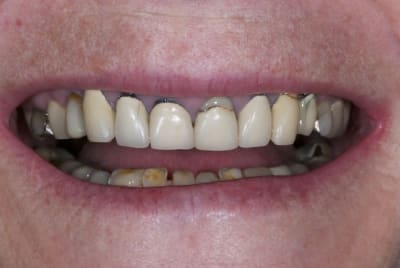

J'ai commencé ce cas récemment, donc je tiendrais a jour ce fil si il est suivit, au fur et à mesure du traitement.

L’intérêt et de confronter nos conceptions et opinions afin pourquoi pas de faire évoluer mon traitement.

La demande concerne la réhabilitation esthétique du bloc incisif supérieur.

On ne parlera pas de bruxisme, de dvo, de gouttière et de réhabilitation globale pour diverses raisons, seule le traitement esthétique de 14 a 24 nous concerne ici et ses différentes solutions pour le traiter.